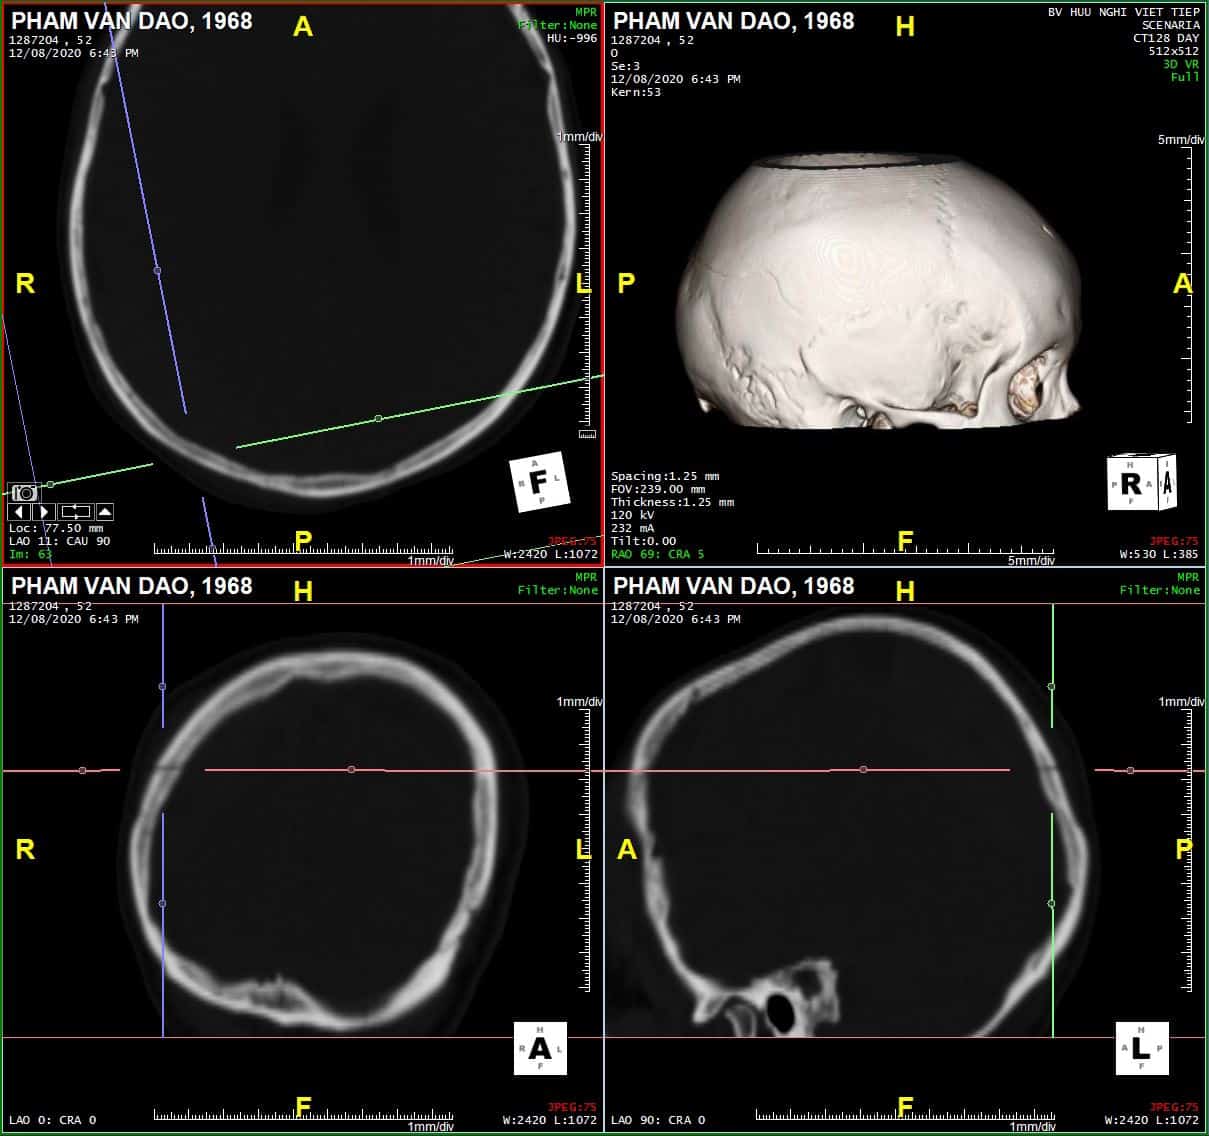

Chấn thương sọ - Ảnh 3

Sagittal

# Tụ máu ngoài màng cứng vùng chẩm phải / Vỡ xương chẩm phải: đường vỡ thẳng (Linear fracture) không thấy rõ trên hướng cắt Axial => quan sát rõ trên hướng cắt Coronal và Sagittal.